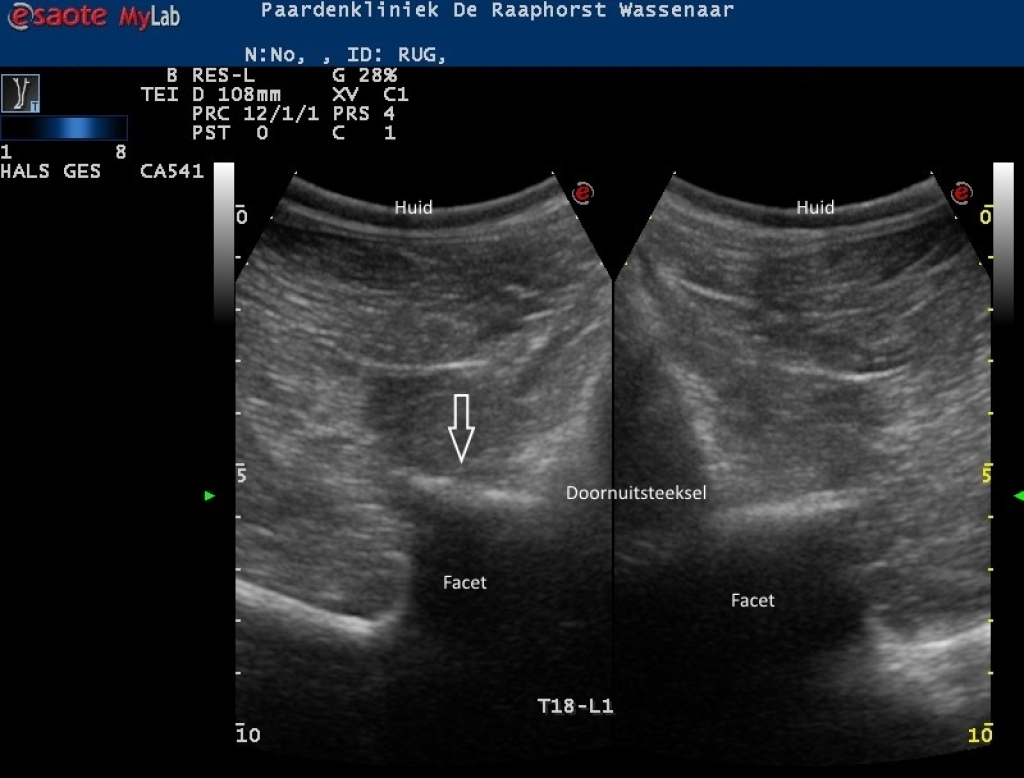

Links: Echobeeld van een licht artrotisch facetgewricht (links) op de thoracolumbale overgang

Echobeeld van een licht artrotisch facetgewricht (links) op de thoracolumbale overgang